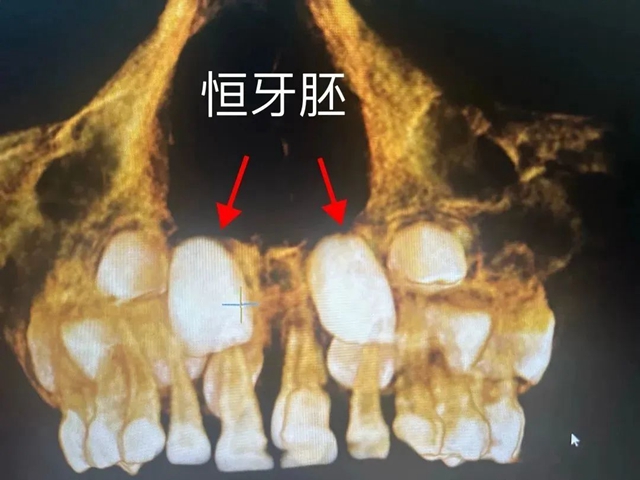

近日,医院口腔科接诊了一位4岁半的小朋友,其上前牙腭侧萌出一颗牙,经CT检查,发现小朋友的上颌两颗中切牙腭侧有两颗多生牙,一颗已萌出并导致其中一颗乳牙牙根被压迫吸收折断并唇向移位,另一颗埋伏阻生,且两颗多生牙占据了恒中切牙牙胚的正常萌出位置。

李颂经详细口内检查,并结合小朋友CT,建议拔除腭侧多生牙及松动乳牙,给恒牙留出足够的萌出通道。但基于小朋友年纪小、配合度差,局麻下拔除会对患儿身心造成影响,李颂联合麻醉科会诊综合评估后,建议在全麻下行无痛拔牙。